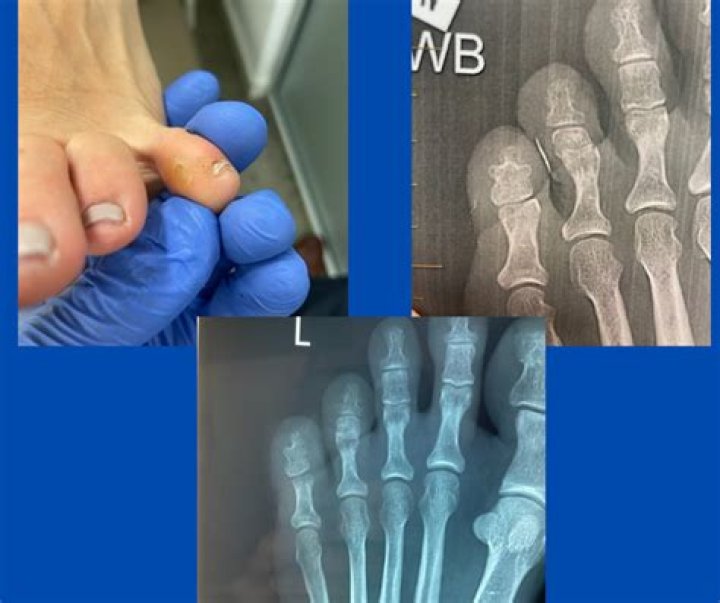

Score: 4.1/5 (50 votes) Interdigital corns or soft corns are the accumulation of spongy, hyperkeratotic, circumscribed tissue between opposing surfaces o...